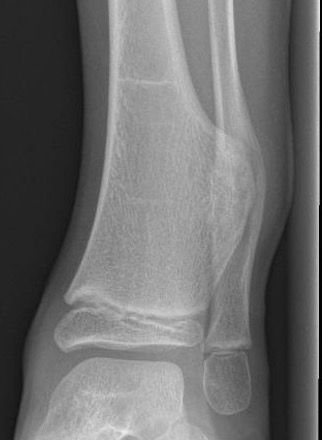

Ankle

Causes valgus deformity

- 19 patients with solitary osteochondroma of distal tibia or fibula

- cause plastic deformity and pronation deformity

- distal tibia more symptomatic than distal fibula

- 4/19 recurred

Appy-Fedida et al J Foot Ankle Surg 2017

- trans-fibular approach for worsening valgus deformity in 10 cases

- good functional outcomes

- recurrence in 1 case

- 7/10 developed tibiofibular synostosis